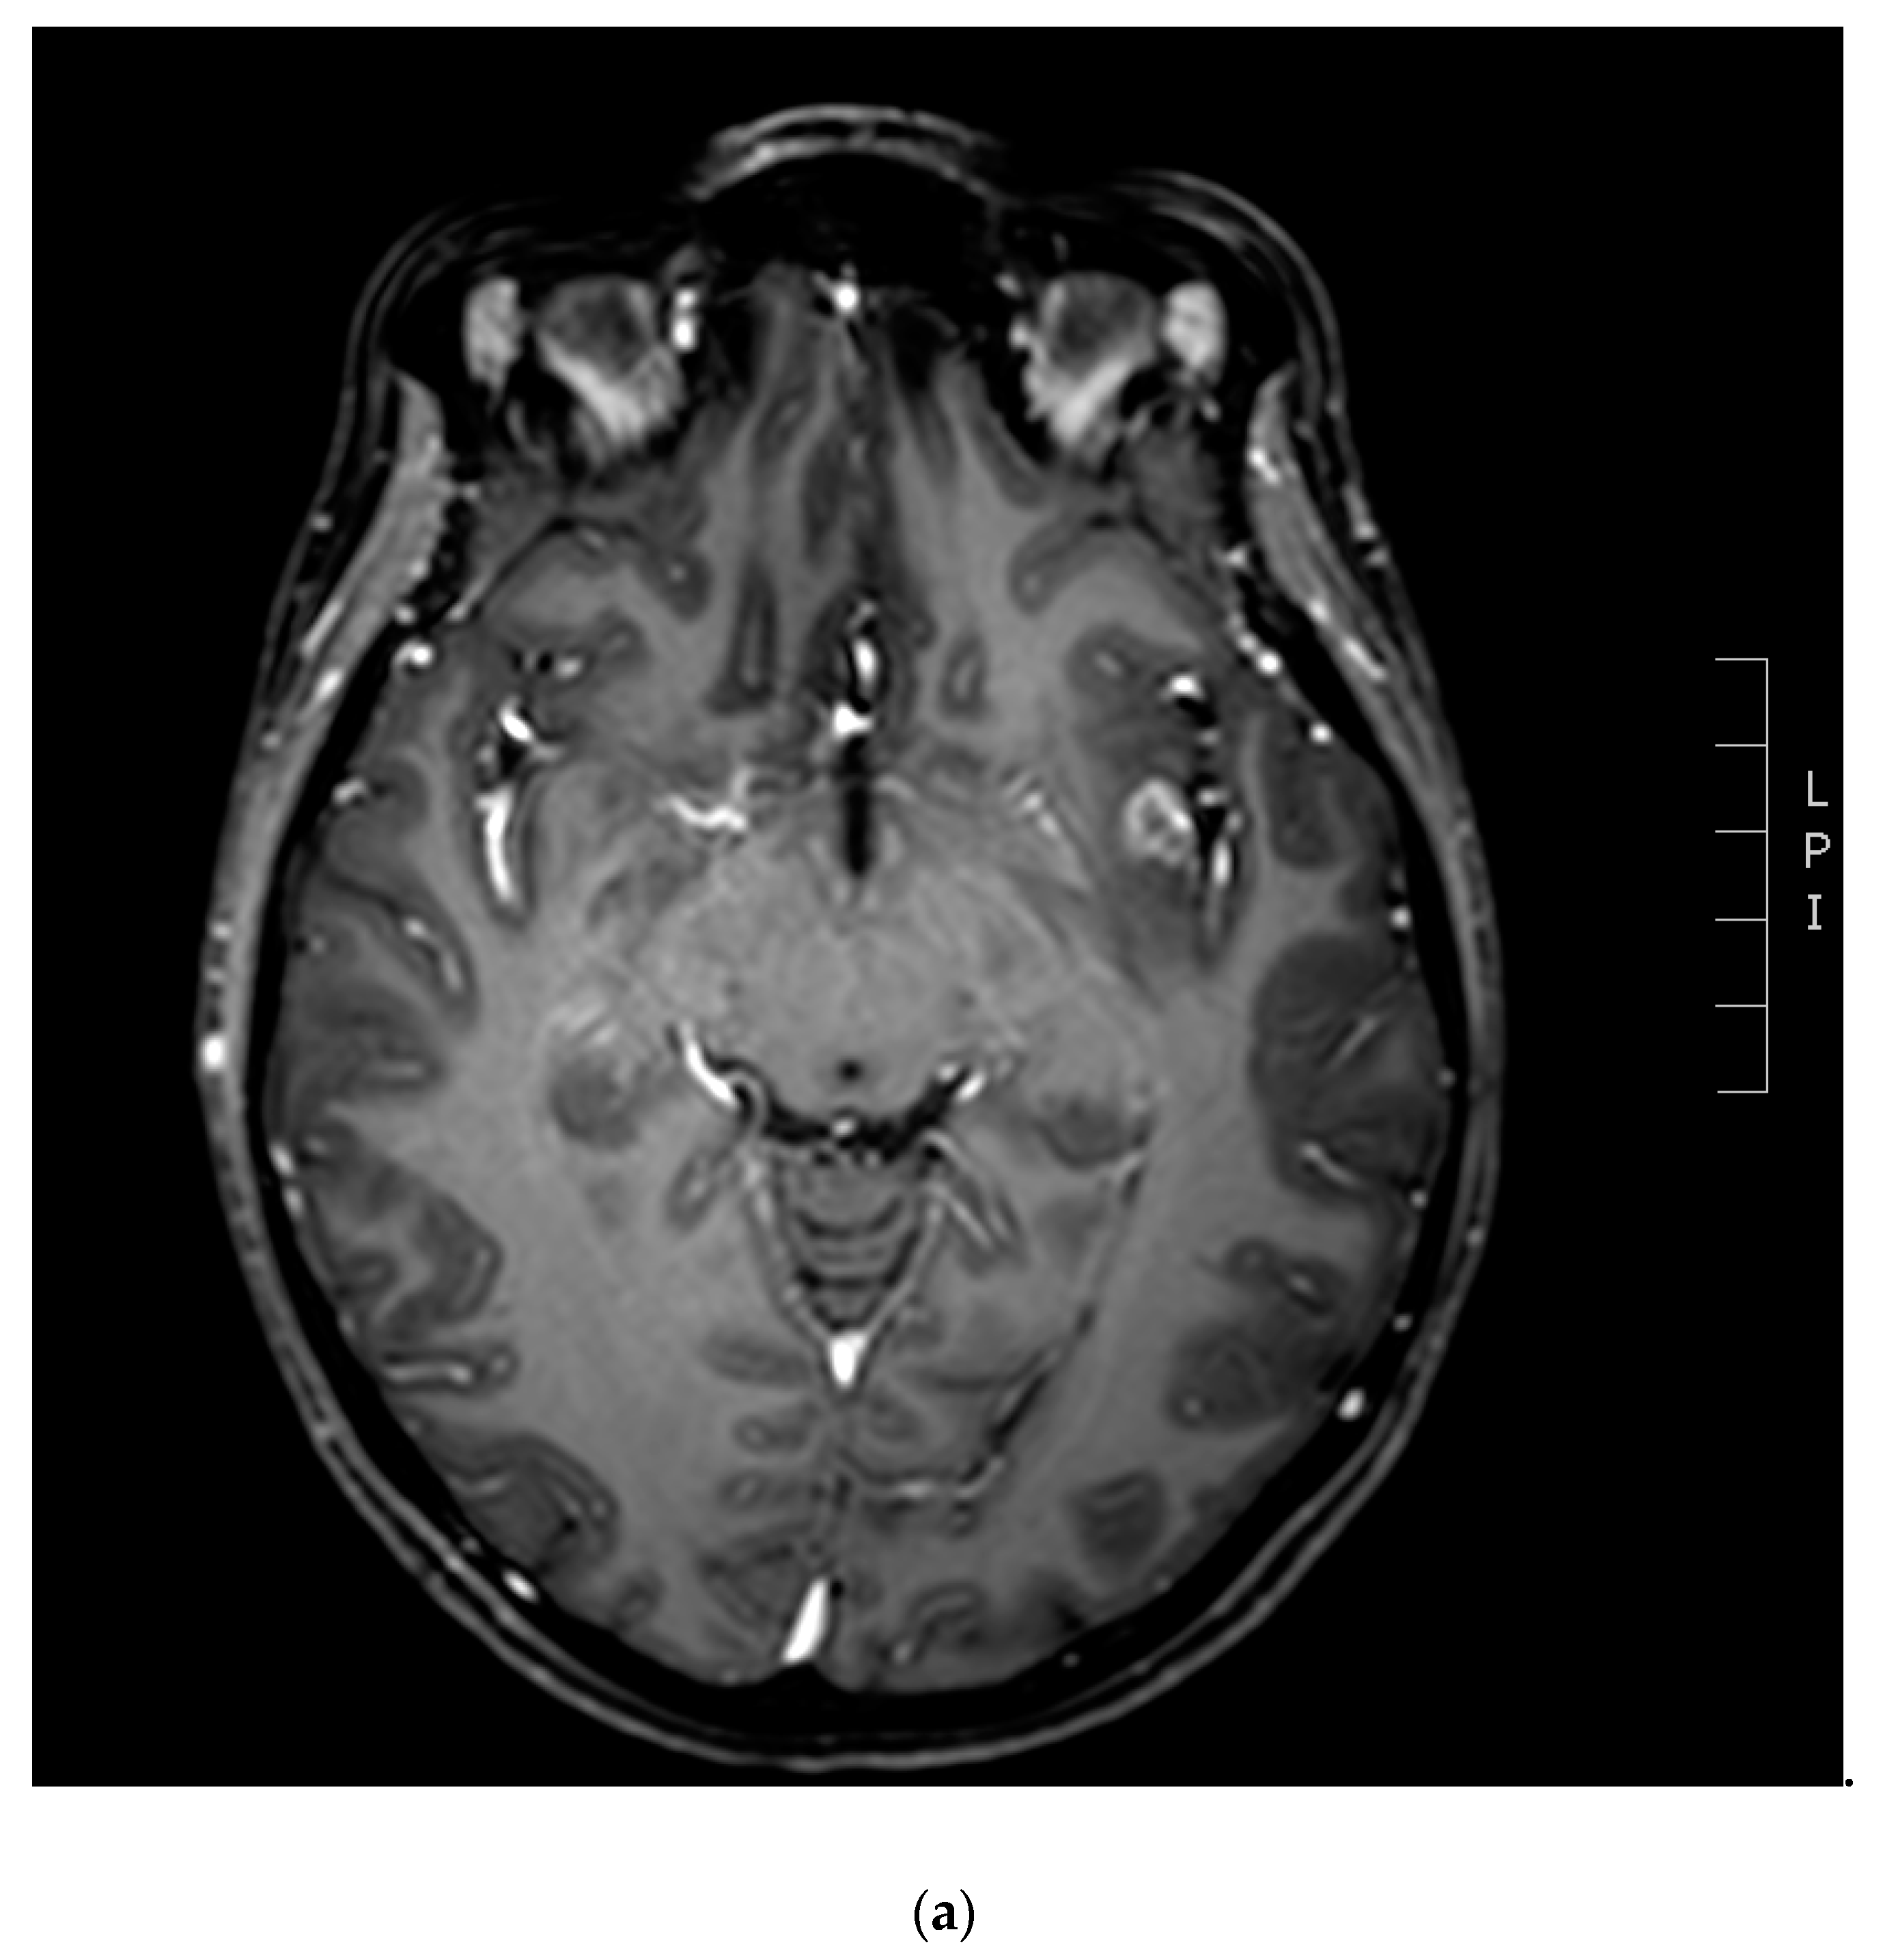

3.1. Diagnostic Imaging Tools in Radionecrosis

3.2. Diffusion and Perfusion MRI